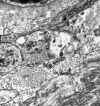

Visualization of severe acute respiratory syndrome coronavirus 2 invading the human placenta using electron microscopy